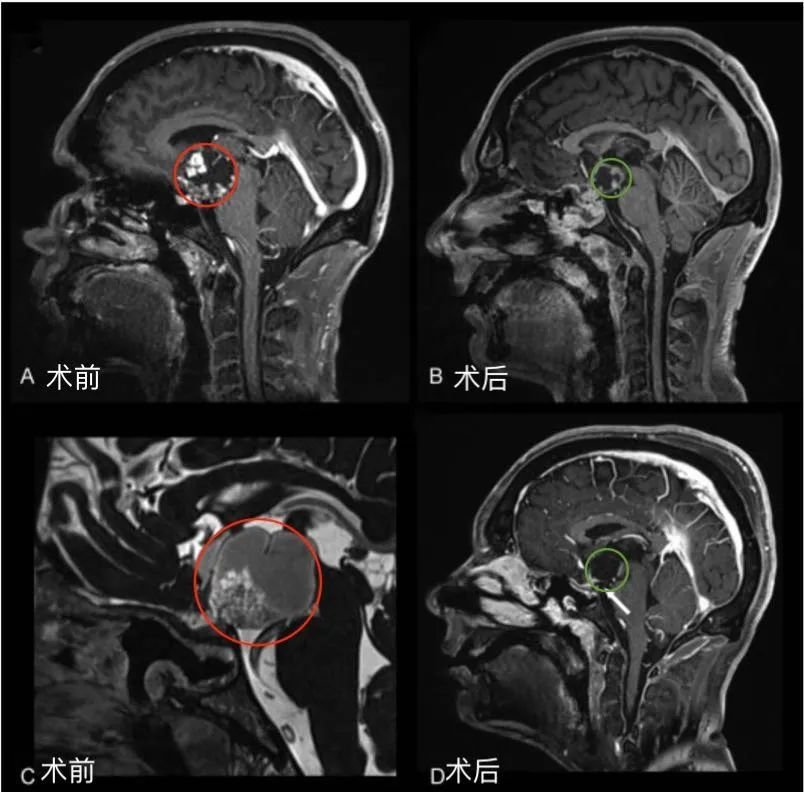

李奶奶的术前术后MRI对比,红色为术前肿瘤位置,绿色为术后切除效果

术前症状:双侧视野同侧缺损(左侧),视物模糊。

术后情况:术后一天ICU查房李奶奶和巴教授愉快交流,复视较术前好转。术后四天普通病房查房李奶奶复视完全好转,状态很好,可以坐起来。术后两周李奶奶恢复良好顺利出院。